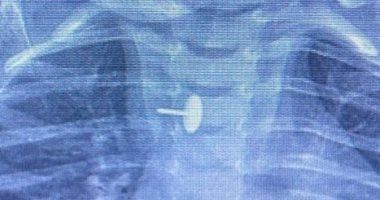

نجح فريق قسم جراحة الأطفال، بمستشفى الأطفال التخصصي ببنها، بمحافظة القليوبية، بقيادة الدكتور محمد متولي رئيس قسم جراحة الأطفال، في إجراء عملية دقيقة لاستخراج دبوس ضغط من مريء طفلة عمرها سنة و7 أشهر، كانت قد ابتلعته منذ 6 أشهر.

الجسم الغريب استقر داخل جدار المرئ

كشفت مستشفى الأطفال التخصصي ببنها، في بيان لها، أن الجسم الغريب استقر داخل جدار المريء، مما تسبب في عدم قدرة الطفلة على البلع طوال هذه الفترة، وجعل حياتها في خطر دائم. استخدام أحدث الأجهزة في الجراحة

دبوس ضغط فى مرئ طفلة